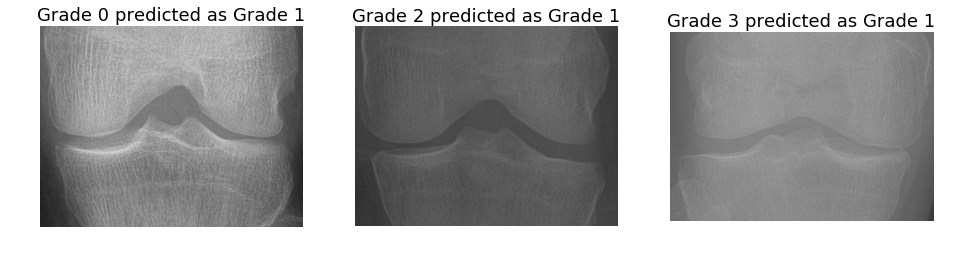

The automatic assessment of knee OA severity has been previously approached in the literature as an image classification problem [1, 3, 4], with the KL grading scale as the ground truth. WNDCHARM111Weighted Neighbor Distance using Compound Hierarchy of Algorithms Representing Morphology, a multi-purpose biomedical image classifier was used to classify knee OA images [4, 5]. High binary classification accuracies (80% to 91%) have been reported using the WNDCHARM classifier for classifying the extreme stages: grade 0 (normal) vs grade 4 (severe), grade 0 vs grade 3 (moderate). However, the classification accuracies of the images belonging to successive grades are low (55% to 65%) and the multi-class classification accuracy is low (35%). The overall classification accuracies of knee OA needs improvement for real-world computer aided diagnosis [1, 3, 6].

Yoo et al. [43] have built a self-assessment scoring system and an artificial neural network (ANN) model for radiographic and symptomatic knee OA risk prediction. In a recent approach, Tiulpin et al. [44] presented a new computer-aided diagnostic approach based on deep Siamese CNNs, which were originally designed to learn a similarity metric between pairs of images. However, rather than comparing image pairs, the authors extend this idea to similarity in knee x-ray images (with 2 symmetric knee joints). Splitting the images at the central position and feeding both knee joints into a separate CNN branch allows the network to learn identical weights for both branches. They outperform the previous approaches by achieving an average multi-class testing accuracy score of 66.7 % on the entire OAI dataset.

There are several approaches in the literature for knee OA image classification that have extracted and tested many image features, such as Haralick textures [41], Gabor textures [2], GLCM textures [42], local binary patterns [40], shape, and statistical features of knee joints [42]. There is even an approach that uses a large set of features based on pixel statistics, object and edge statistics, texture, histograms, and transforms [7, 5, 4]. Different classifiers have been tested for knee OA images classification such as k-Nearest Neighbour [40, 1], SVM [41], and random forest classifiers [2]. However, all these approaches have achieved low multi-class classification accuracy, and in particular classifying successive grade knee OA images still remains a challenging task. There is a need for a highly accurate real world automated system that can be used as a support system by clinicians and medical practitioners for knee OA diagnosis.